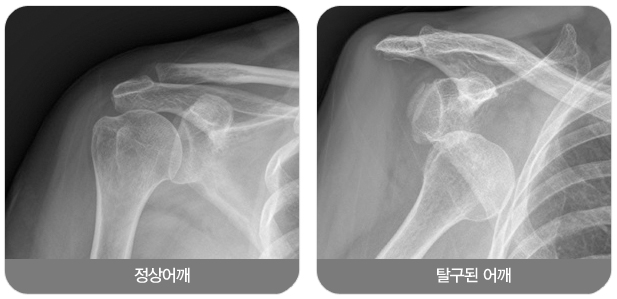

![]()

급성 탈구인 경우 진찰소견과 엑스레이 소견을 보고 탈구의 방향을 조사하는데 대부분의 경우 팔이 앞쪽으로 빠지는 전방 탈구입니다. 재발성 탈구가 되면 MRI 등으로 관절순 또는 인대들의 상태를 분석하는 것이 필요합니다. 또한 재발성 탈구시 골절을 동반하는 경우와 골결손이 심하면 수술전 CT사진이 필요합니다.